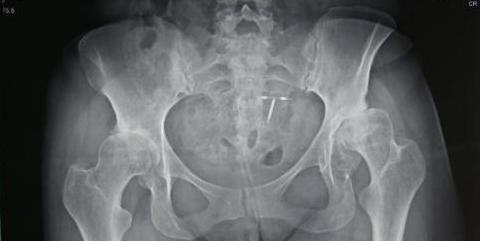

Bilateral hip replacement

Marciela Arevalo is one of our younger patients to undergo bilateral hip replacement during the 2018 CAMTA mission. Marciela is 45 years old. Born with hip dysplasia both hips have degenerated considerably, her left far more than her right. She ran an empanada stand until her hips were too sore for her to work standing all day.

The left femoral head was almost moving out side of the acetabulum (hip socket)